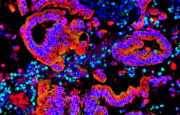

Bauchspeicheldrüsenkrebs: Neue Mechanismen der Beeinflussung durch das Immunsystem entschlüsselt

Forschende der Universitätsmedizin Göttingen (UMG) haben neue Wechselwirkungen zwischen Pankreaskarzinomzellen und dem Immunsystem aufgedeckt. Die Erkenntnisse liefern wichtige Ansätze für innovative Therapien.

Um die Therapie des Pankreaskarzinoms verbessern zu können, haben Forschende die molekularen Mechanismen in den Tumorzellen genauer untersucht und erstmals festgestellt, dass sich deren molekulare Identität pharmakologisch beeinflussen lässt – mit einem Wirkstoff, der bereits bei der aggressiven Krebsart eingesetzt wird.